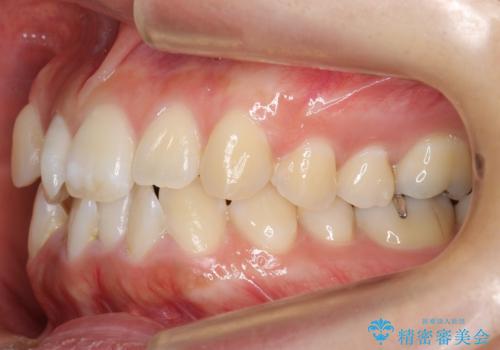

真ん中が右にずれている 前歯のがたつき 治療途中に地方へ引っ越したが、通ってワイヤー矯正

- 前歯のがたつきを主訴に来院。

前歯のクロスバイト、上の前歯の正中が右にずれていました。

右上の奥歯の高さもない状態でしたが、矯正治療が終わってからしっかりかぶせました。

上下左右の小臼歯を抜歯しています。